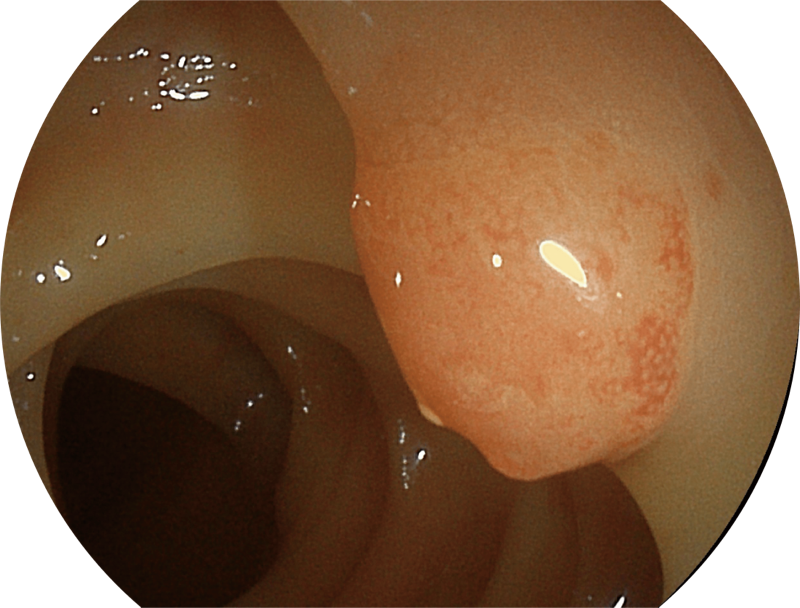

(Versatile Intelligent Staining Technology)

能够凸显黏膜浅层血管轮廓和黏膜表面微结构,适用于中、近景观察下的早癌精确诊断。